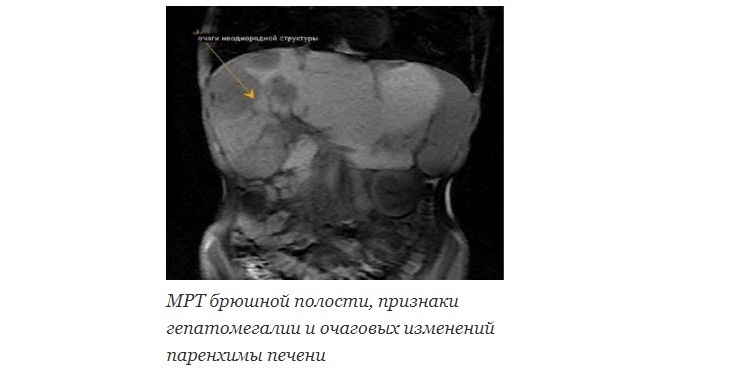

Инструментальная диагностика

Дает ценную информацию об изменениях паренхимы печени и рядом расположенных структур. Лучшими тестами я считаю:

- УЗИ (ультразвуковое исследование).

- КТ, МРТ (компьютерная и магнитно-резонансная томография).

- Пункционная биопсия – то есть взятие фрагмента ткани печени для исследования под микроскопом.

УЗИ, КТ и МРТ – это методы визуализации, то есть отображения исследуемых структур на экране аппарата или снимках. Они позволяют выявить как объемные образования (абсцессы, опухоли), так и признаки диффузных изменений печени (что свойственно, прежде всего, циррозу).